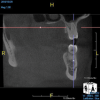

(4.) In a CBCT image axial view, the MB1 and MB2 canals are readily visible in tooth No. 14, and in the coronal view, these two separate canals can be seen to merge into a single apical opening.

Figure 4

(5.) In a CBCT image axial view, the MB1 and MB2 canals are readily visible in tooth No. 14, and in the coronal view, these two separate canals can be seen to merge into a single apical opening.

Figure 5

Being able to see the number and shape of the canals accurately prior to treatment is the desire of any clinician who performs endodontics. Research suggests that, due to improved diagnostic accuracy, the final treatment plan may change in up to 50% of endodontic cases if CBCT is used rather than traditional 2D imaging.14,15 The question of whether or not a patient has an MB2 canal can be answered prior to opening the access preparation (Figure 4 and Figure 5). Visualizing single canals that bifurcate in the apical or middle third of the root or those that merge to a single apical opening can help clinicians to understand their instrumentation needs in advance. In addition, the ability to measure the length and shape of a canal planned for instrumentation prior to utilizing an apex locator helps to confirm any measurements obtained by other means. It should also be noted that the ability to see a pathosis in 3 dimensions and to involve the patient in understanding his or her condition prior to any decision-making allows for definitive treatment planning. In fact, many patients have pathoses associated with teeth that are asymptomatic that remain unknown to them until they are visually presented with the evidence (Figure 6).